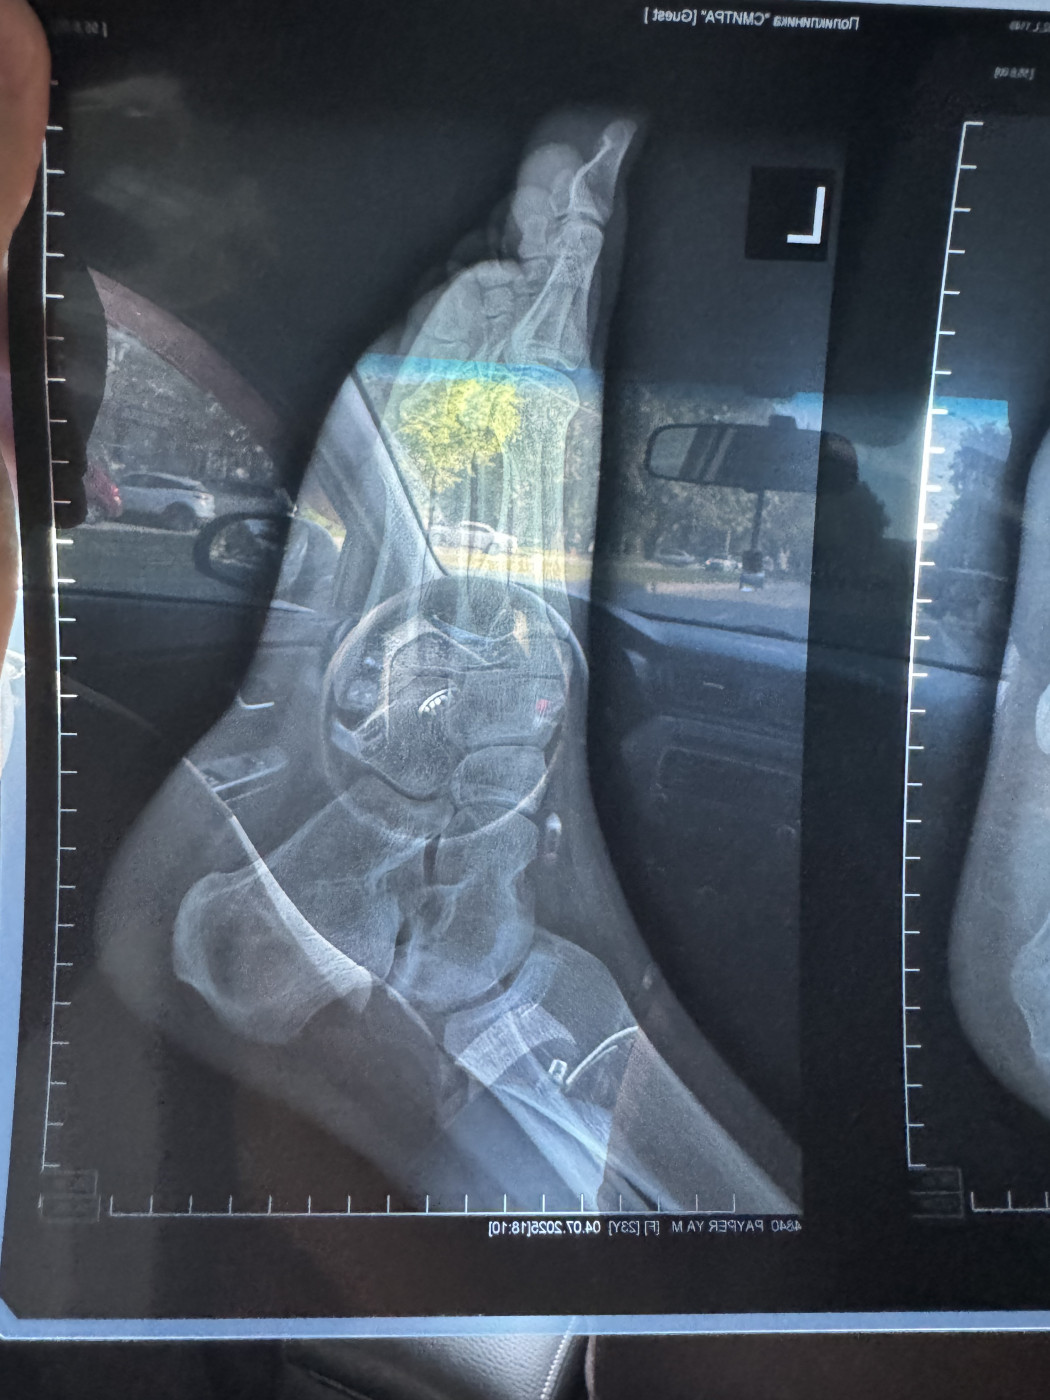

Перелом пятки и реабилитация   1 ответ

Здравствуйте 10.06 сломала пятку прыгнула с высоты, 04.07 сделал новый рентген хотела бы узнать рекомендации, В данный момент нога в жестком ортезе, не отекает и не болит ,сегодня 6 недель и 2 дня со дня перелома

Протокол исследования:Визуализируется: в левой пяточной кости определяется консолидирующийся перелом тела пяточной кости без смещения.…